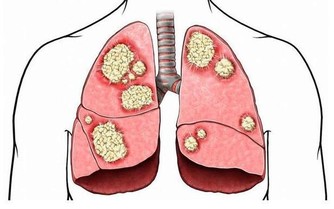

腎積水是一種慢性腎髒病,腎積水的成因是由於腎結石堵塞導致尿液聚積在腎臟內,不能及時排出。如果結石不能及時排出,長時間腎積水,久而久之就會影響到腎臟的功能。

但是現代都市人的生活飲食習慣越來越不規律,亂吃亂喝、暴飲暴食、飲食作息不規律都是可以導致腎結石。特別是以下幾種食物,吃多了都是很容易患上腎結石的。